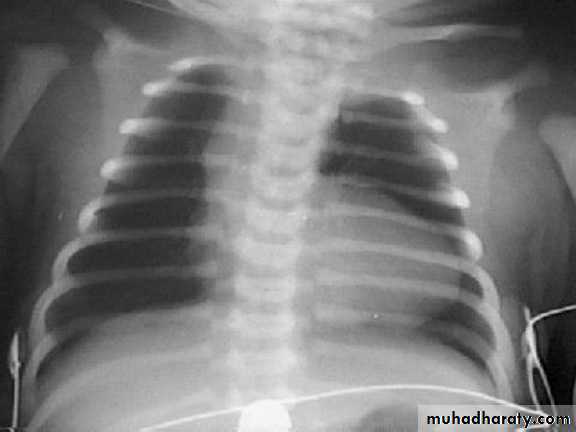

• Chest x-ray—varying heart enlargement (right ventricular and right atrial); Increased pulmonary vessel markings, edema• ECG—right-axis deviation and RVH

CXR : Boot-shaped heartComplications: